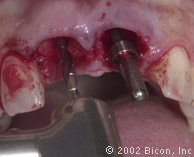

Вид спустя десять недель после установки имплантантов

Установка двух 3.0mm Impression Post

Подготовка к установке постоянной конструкции

Произведены послабляющие разрезы

Установка готовых конструкций